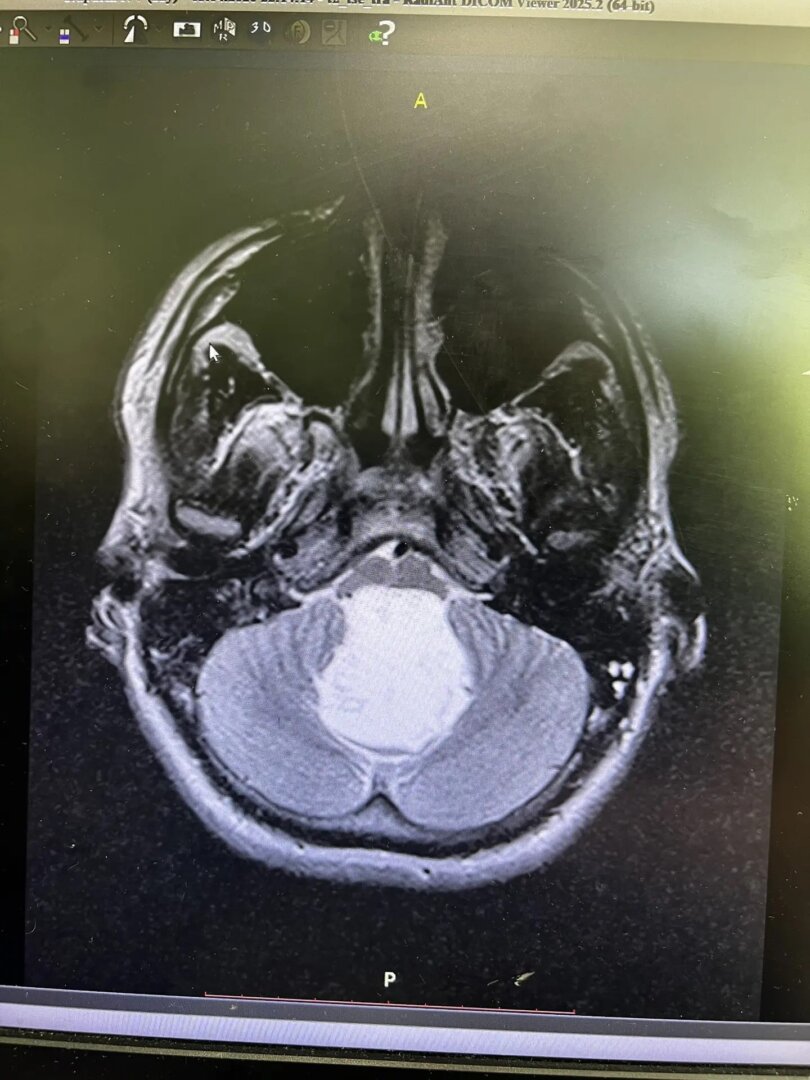

Нейрохирург Шалиндер Аул отметил, что внешний вид опухоли на снимке был поразительным. Холестеатома, или эпидермоидная киста, представляет собой доброкачественное новообразование белого цвета с перламутровым оттенком. Это редкое заболевание встречается у 3-9 человек на каждые 100 тысяч населения.

Операция длилась почти семь часов. Шалиндер Аул и его коллега Ильяс Кылданов удалили опухоль размером 6 на 4,5 сантиметра, которая передавила ствол мозга. Результаты гистологии показали, что у Никиты врожденное доброкачественное новообразование, которое не проявляло себя до тех пор, пока не перекрыло пути для спинномозговой жидкости.